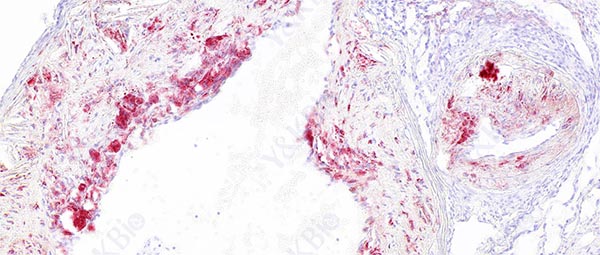

新疆冰冻切片是一种常见的组织学技术,用于制备组织标本以供显微镜观察。为了预防冰晶形成,可以采取的措施包括适当固定组织、适当处理组织、使用适当的冷冻介质、控制切片速度、注意环境温度和湿度等。